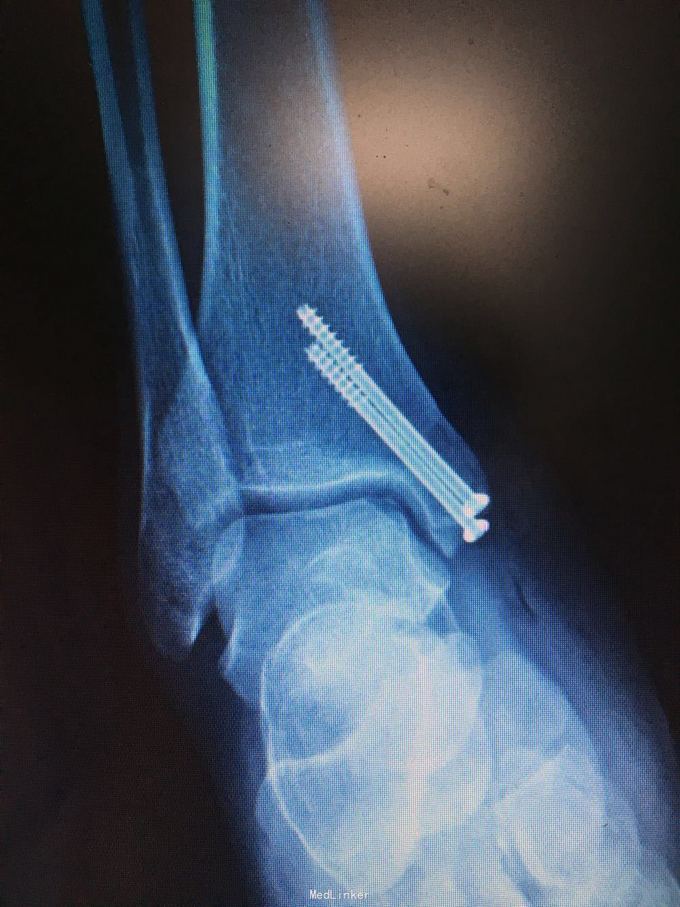

诊断和手术方式如题 直接上图

术后第二天进行非负重下踝泵练习,2周内限制踝关节外翻和外旋,6-8周后根据骨愈合情况下地负重 目前有北京积水潭报道全关节镜下完成此手术,我们将进一步探索,另外,股骨外侧髁非负重区取骨后膝关节痛的情况可见,取骨区域尚需改进